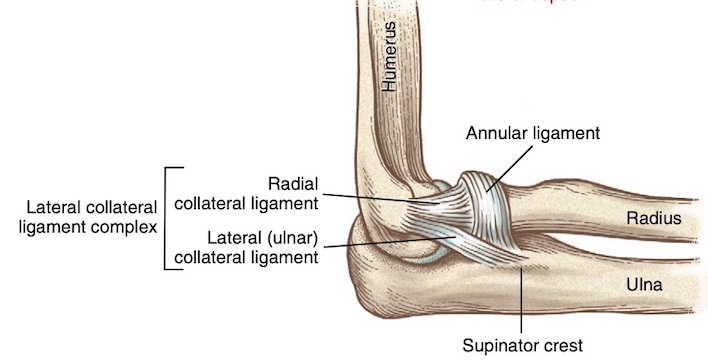

- Phức hợp dây chằng bên ngoài (Hình 2) bao gồm dây chằng bên quay, dây chằng vòng quay (annular ligament), và dây chằng bên trụ ngoài (lateral ulnar collateral ligament). Dây chằng bên trụ ngoài đóng góp nhiều nhất vào sự ổn định ở mặt ngoài của khớp khuỷu. Tổn thương cấu trúc này có thể dẫn đến mất vững xoay sau ngoài.